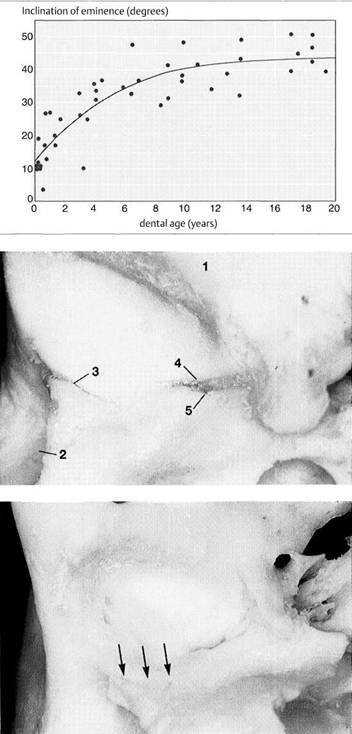

Inclination

of the articular

protuberance to the occlusal

plane

This graph (adapted from that of Nickel et al. 1988) indicates the inclination of the posterior slope of the eminence (articular protuberance) in relation to the occlusal plane. Accordingly, at the age of 3 years the eminence has reached 50% of its final shape (Nickel et al. 1997). Between the tenth and twentieth year there is a difference of only 5°. The study material originates from the osteological collection of Hamman-Todd and Johns Hopkins, Cleveland Museum of Natural History.

Joint

region of the temporal

bone

Inferior view of the temporal portion of a defleshed temporomandibular joint. Near the upper border of the picture is the articular eminence (1) and at the far left is the external auditory meatus (2). In the posterior portion of the fossa the squamotympanic fissure (3) is found laterally, and the petrosquamous (4) and petrotympanic (5) fissures are found medially. Both the superior stratum of the bilaminar zone and the posterior portion of the joint capsule, and sometimes also the fascia of the parotid gland can insert into these fissures.

Ossification

of the fissures

and disk displacement

Inferior view of a temporal bone with partially ossified fissures. The lateral half of the squamotympanic fissure is completely ossified (arrows). The superior stratum of the bilaminar zone can now insert only into the periosteum in this region. It has been shown that these fissures are ossified in more than 95% of patients with disk displacement, whereas in joints without disk displacement normal fissure formation prevails (Bumann et al. 1991).